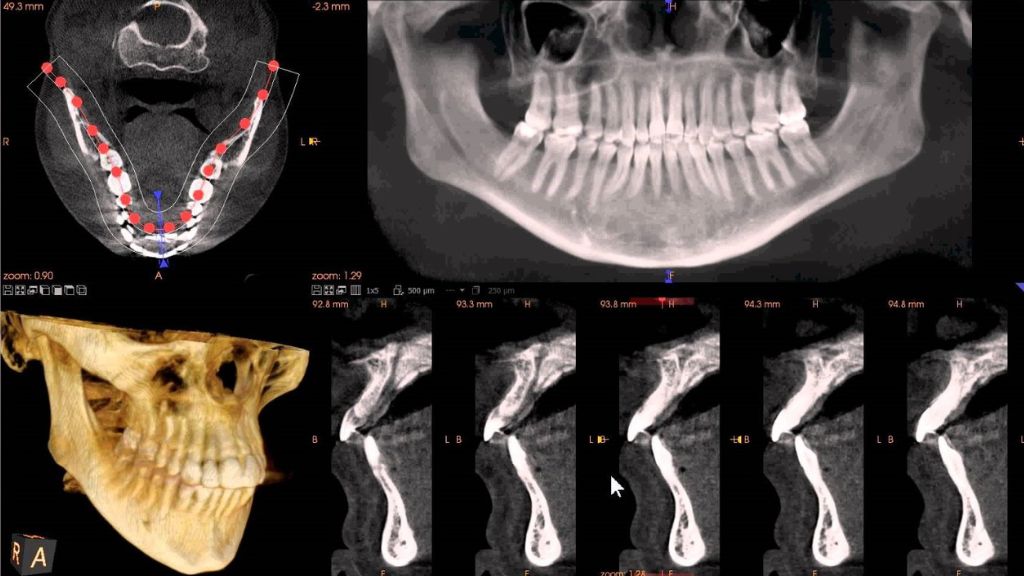

Implant planning

Detection of pathology

Cephalometric tracings

Bone density assessment

Airway assessment

Maxillary sinus assessment

TMJ views and assessment